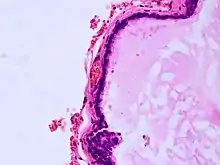

Histopathology of colloid cyst |

A colloid cyst is a non-malignant tumor in the brain. It consists of a gelatinous material contained within a membrane of epithelial tissue. It is almost always found just posterior to the foramen of Monro in the anterior aspect of the third ventricle, originating from the roof of the ventricle. Because of its location, it can cause obstructive hydrocephalus and increased intracranial pressure. Colloid cysts represent 0.5–1.0% of intracranial tumors.[1]